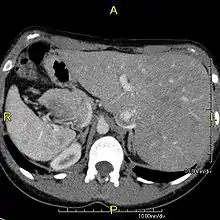

Axial CT image showing situs inversus (liver and IVC on the left, spleen and aorta on the right) in a patient with Kartagener syndrome.

The condition affects all major structures within the thorax and abdomen. Generally, the organs are simply transposed through the sagittal plane. The heart is located on the right side of the thorax, the stomach and spleen on the right side of the abdomen and the liver and gall bladder on the left side. The heart's normal right atrium occurs on the left, and the left atrium is on the right. The lung anatomy is reversed and the left lung has three lobes while the right lung has two lobes. The intestines and other internal structures are also reversed from the normal, and the blood vessels, nerves, and lymphatics are also transposed.

Situs inversus is found in about 0.01% of the population, or about 1 person in 10,000. In the most common situation, situs inversus totalis, it involves complete transposition (right to left reversal) of all of the viscera. The heart is not in its usual position in the left chest, but is on the right, a condition known as dextrocardia (literally, "right-hearted"). Because the relationship between the organs is not changed, most people with situs inversus have no associated medical symptoms or complications.[1]